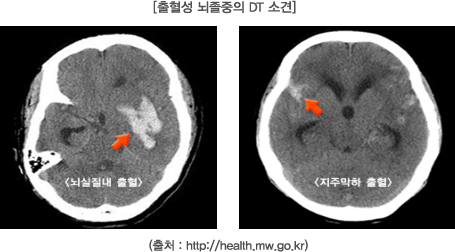

- ๋ณ์์ ๋์ฐฉํ๋ฉด CT ๋๋ MRI ๊ฒ์ฌ, ํ๊ด์ดฌ์ ๋ฑ์ด ์ด๋ฃจ์ด์ ธ ์์ธ ๊ท๋ช ๋ฐ ์น๋ฃ๊ณํ์ด ์ธ์์ง๋๋ค. PMC

๋๊ฒฝ์ ์ ์กฐ์ฆ์์ด ์์ฌ๋ ๋๋ MRI๋ CT ๊ฒ์ฌ๋ก ํ๊ด ์ํ๋ฅผ ์ ํํ ํ์ธํ๋ ๊ฒ์ด ์ค์ํฉ๋๋ค.

MRI๋ ํ๋ฅ ์ฐจ๋จ ๋ถ์๋ฅผ ์ธ๋ฐํ ๋ณผ ์ ์๊ณ , CT๋ ์ถํ ์ฌ๋ถ๋ฅผ ๋น ๋ฅด๊ฒ ํ์

ํ ์ ์์ต๋๋ค.